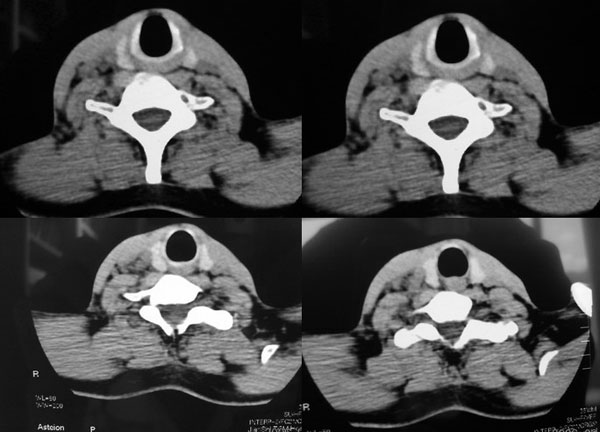

患者,谭××,男,35岁,右颈部肿痛一周,体温39度。增强待续,伪影大,对不起,请大家凑合……

右侧颈部软组织肿块,边界清楚,中心坏死,与周边软组织同步强化,多考虑:肿大淋巴结.不除外神经鞘膜瘤.

右颈部肌肉、血管间隙内可见不规则肿块,强化后呈多房性,间隔及壁线样强化,考虑颈部脓肿。

颈部血管间多房囊性肿块,边缘模糊,增强囊壁有强化,中间低密度区无强化。从强化特点支持颈部神经鞘瘤及淋巴性肿瘤。但病人病史较短,且有高热,病灶边缘模糊,又都不支持。神经鞘瘤及淋巴性肿瘤多边缘清楚。因此还是考虑炎症。

中心性坏死,环行强化支持:(1 淋巴结核)(2 脓肿) 临床高热,后者可能性更大 。神经鞘膜瘤不会广泛弥漫性的延续至上纵隔。